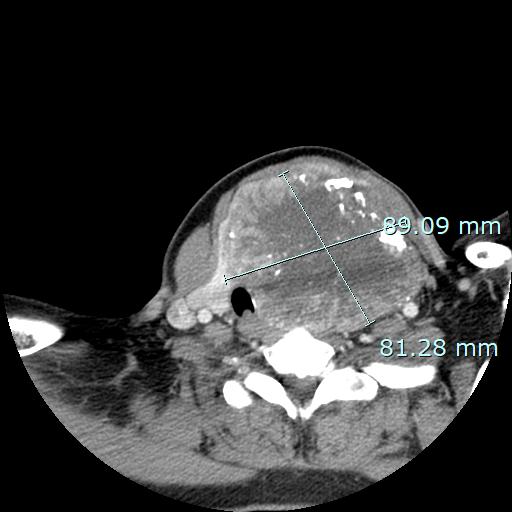

40대 여성분으로, 23년도 중순 쯤 내원하여, 당시 숨쉬는 소리가 거친 문제가 있었지만 의사소통이 원활하지 않아 숨차는 증상이 심했는지까지는 정확히 알 도리는 없었습니다. CT에서 기관지가 우측으로 상당히 편위되었고, 종양은 척추에 까지 닿아있는 양상입니다. 이 정도 크기임에도 성대 마비는 없었던 탓에, 위험한 병은 아닐 것임을 일단 짐작할 수 있었습니다.

10cm 짜리 갑상선 혹을 안전하게 제거하였고, 최종 병리 결과는 갑상선 여포성 질환(thyroid follicular nodular disease)라는 양성 종양으로 확인되었습니다.